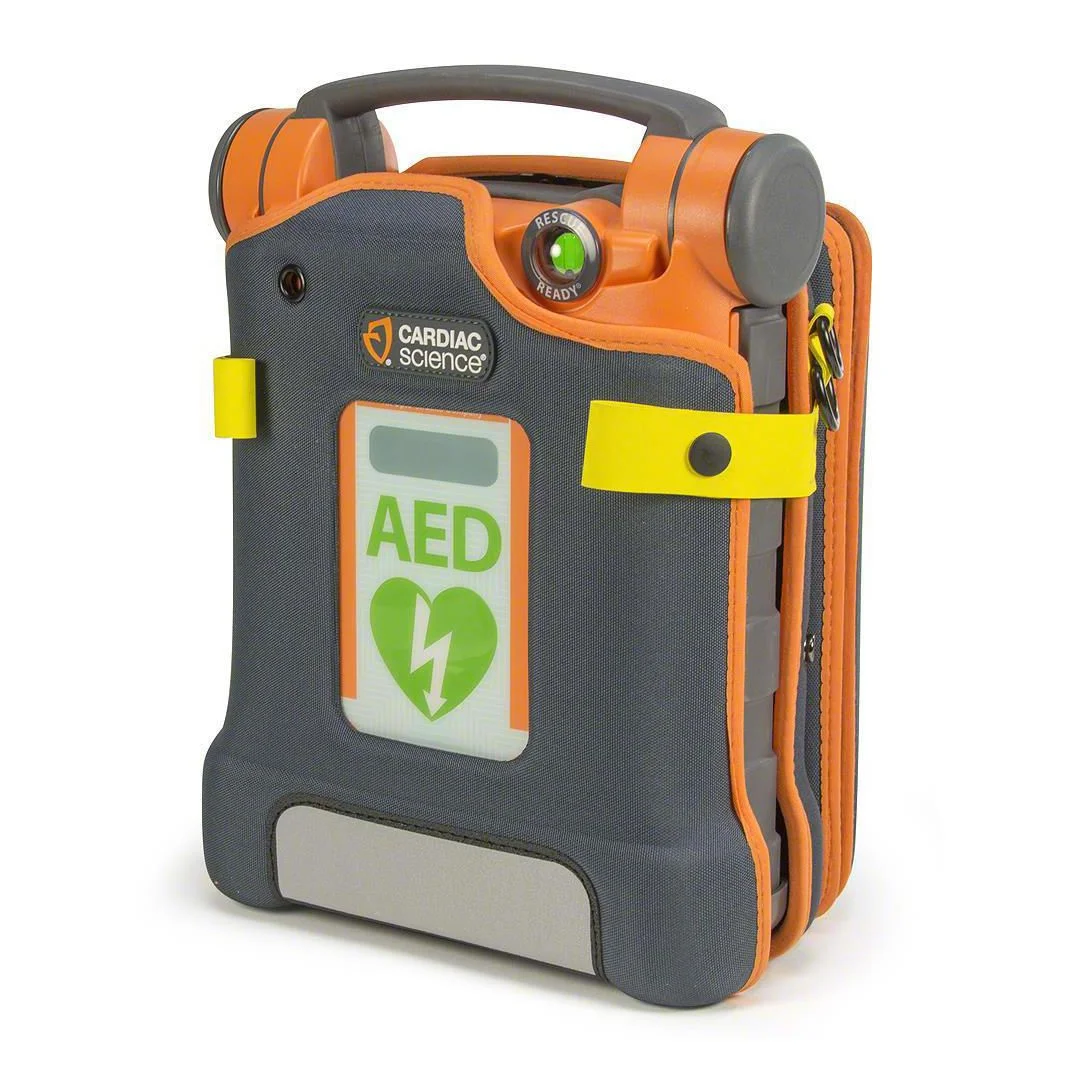

Powerheart G5 er en hjertestarter med fremtidens teknologi som sikrer trygg og sikker behandling av pasienten. De kraftige egenskapene til Powerheart G5 er laget for å gi en pasient med plutselig og akutt hjertestans, best sjanse til å overleve. Denne modellen gir tilbakemelding på kvaliteten av hjertekompresjonene.

Powerheart G5 tester seg selv og sine systemer hver dag, som vil si at den alltid er operativ. Den tilbyr både norsk og engelsk talemelding med bruksinformasjon. Den er svært brukervennlig med gode høyttalere og et tekst-display som egner seg godt til steder der det kan være en del støy.

Pakken inneholder: Hjertestarter, brukerveiledning, batteri- og elektrodesett med kompresjonsmåler.

- Robust, pålitelig og alltid på vakt

- Svært brukervennlig

- Høy tetthetsgrad (IP55) mot støv og vann for ytelse i tøffe og utfordrende miljøer

- Oppfyller strenge militære standarder for sjokk, vibrasjoner og slipp testing

- RescueReady ®-teknologi kontrollerer selv alle de viktigste komponenter i maskinen

- Fullfører en delvis oppladet spenning ukentlig, og en full ladet månedlig, for å teste maskinens evne

- 8-års garanti

- Medisinsk godkjent batteri med en 4-års full operativ garanti

- RescueCoach ™ veileder brukerne gjennom hvert kritisk trinn ved en hjertestans

- Bytt til et engelsk språk under en hjertestans med et trykk på en knapp

- Bruker mindre en 10 sekunder på å analysere hjerterytme og levere sjokk

- Vurderer pasientens behov og leverer et tilpasset sjokk på et passende energinivå

- Oppdager automatisk barneelektroder og leverer en redusert energi

- Enkelt å oppdatere innstillingene hvis retningslinjene endres

- Raskt å overføre/ gjennomgå data via USB

- Hjertestarterelektroden gir tilbakemelding på kvaliteten av brystkompresjonene